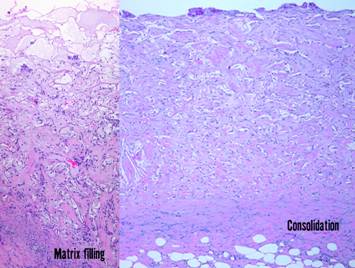

Pictured is matrix regeneration within a piece of Integra collagen-gag matrix.  It is no longer the non-living empty matrix placed on the original wound, but a fully restored living material.  The details of this process are now presented.  However, even without knowing the specific details, it can be appreciated that the structure, morphology, and patterns of this regenerated biological material are different than the microscopic structure of the normal post-inflammatory wound.  Normal wound healing is triggered by inflammation and then evolves according to its own “program” of how angiocytes and fibroblasts rebuild a stroma of blood vessels and connective mesh.  Integra suppresses inflammation, and thus the normal “wound healing program” is never turned on.  Integra “heals” by a fundamentally different mechanism analogous to embryonic tissue generation.  Its build to a state of complete regeneration is uniform throughout the matrix, distributed rather than stratified, and when complete, it has created a new material that has characteristics mostly like normal dermis and quite unlike scar.  The matrix coaxes the same two cells, angiocytes and fibroblasts, to make a new tissue of blood vessels and connective mesh in a patterned morphology that is profoundly different then scar.  The same cells, making the same elemental components, assemble them in a completely different pattern than wound healing and scar because the embryogenesis-and-stromal-generation “program” is entirely different than the healing-and-scar “program”.

Left upper, the forearm contracture shown in a previous panel.  Integra was used to reconstruct skin after first excising the contracted scar.  Late results show no scar, no scar hypertrophy, no contractures.  Left lower, a keloid excised from behind the ear, skin then reconstructed preemptively with Integra to prevent recurrent keloid.  Late photo shows the area healed with no signs of scar hypertrophy.  Right, a pane of comparative histology.  Top row shows normal dermis, one view having been cut parallel to skin tension lines, the other orthogonal.  Whether seen on side or on end, normal dermis with normal elasticity and has an architecture of collagen bundles separated or porated with interstitial spaces which give it some deformability and pliability, typically greater in one direction than the other.  Middle row shows young scar and young Integra.  The scar is dense in collagen, no spaces, no opportunities for shifting and rolling of bundles, all oriented into locally thick bands but without an overall uniform direction, making the scar anisotropically stiff.  In comparison, young Integra has local fibrous foci which are separated from each other by the matrix, thereby maintaining interstitial porosity and the ability of domains to shift or distend relative to each other, a configuration and mechanics much more like normal dermis.  Bottom row shows scar and Integra in phases of late maturation after many years.  Both have remodeled away from their original appearance back toward normal dermis or fascia,  The difference is that young scar quickly becomes packed with immobile excessively dense collagen, and then it takes years to remodel back to normal stromal density, architecture, and mechanics.  Integra-CGM also takes years to remodel back to a strictly normal appearance, but it has the fundamental architectural and mechanical features of normal dermis right from the very beginning.